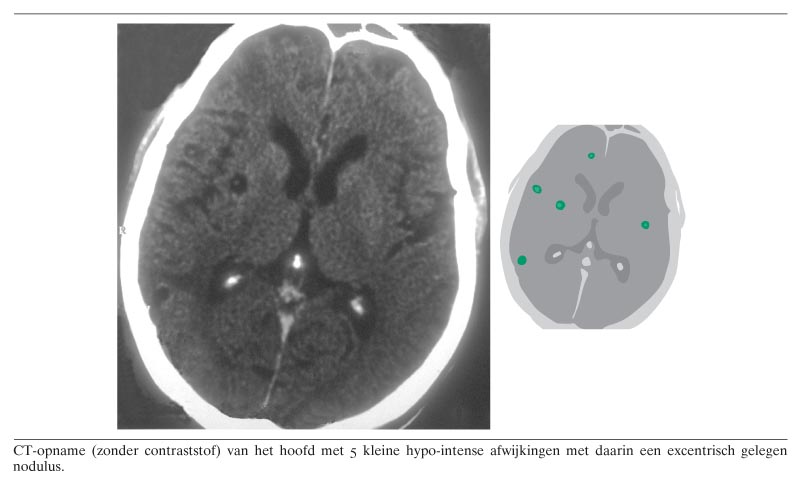

Een 56-jarige Nicaraguaanse man met een blanco voorgeschiedenis werd door een lokale gezondheidsmedewerker verwezen vanwege epilepsie. Heteroanamnestisch bleek het te gaan om een epileptisch insult, hetgeen in de afgelopen maand tweemaal was voorgekomen. Bij het neurologisch onderzoek werden geen afwijkingen gevonden. Bij laboratoriumonderzoek was er alleen een lichte eosinofilie. Gezien het vermoeden van een ruimte-innemend proces werd CT verricht. Daarbij vielen 5 kleine hypo-intense afwijkingen op met daarin een excentrisch gelegen nodulus (figuur). Dit beeld kan goed passen bij neurocysticercose. Daarbij is de nodulus de kop (scolex) van de larve. De veroorzaker is de varkenslintworm (Taenia